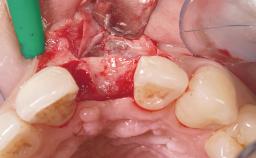

Early Placement of an Implant in a Maxillary Right Central Incisor Site

This 41-year-old female patient was referred to the clinic for the replacement of the right central incisor, since the tooth had developed a root fracture in the long axis that made extraction necessary. The healthy, non-smoking patient was first seen with the tooth still in place. A detailed Esthetic Risk Assessment was performed.The patient was worried about her dental esthetics and had high expectations for a successful treatment outcome from an esthetic point of view. The patient had a medium lip line that displayed parts of the gingiva in the anterior maxilla upon smile.

| Bone Volume | Deficient horizontally, allowing simultaneous augumentation |